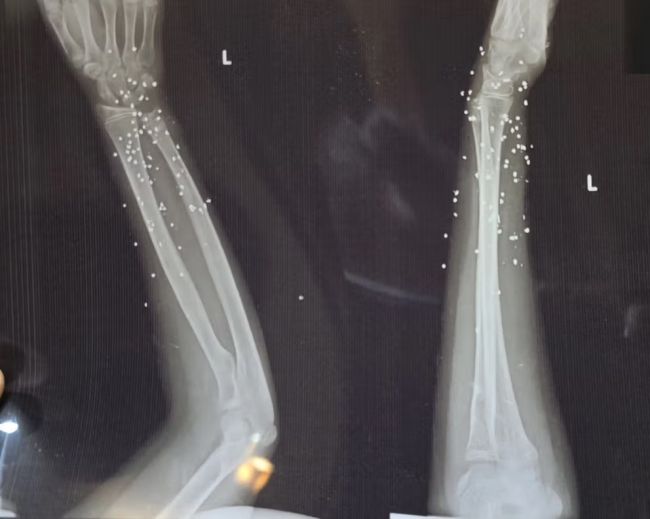

گاردین در گزارش خود تاکید کرد که در برخی تصاویر، تنها یک یا دو ساچمه در جمجمه دیده می‌شود که پس از عبور از چشم در حفره آن متوقف شده‌اند.

در موارد دیگر، صدها ساچمه در بدن پراکنده شده و بافت نرم را تخریب کرده‌اند.

در پرونده «علی»، بیش از ۱۷۴ ساچمه در قفسه سینه راست دیده می‌شود. تراکمی که نشان می‌دهد شلیک از فاصله بسیار نزدیک انجام شده است. ریه راست او آسیب شدید دیده و تجمع خون و هوا در اطراف آن مشاهده می‌شود.

کارشناسان پزشکی گفته‌اند حتی با مداخله فوری، خطر مرگ در چنین شرایطی بالاست.اصابت ساچمه یا گلوله به اندام تناسلی و پیامدهای بلندمدت